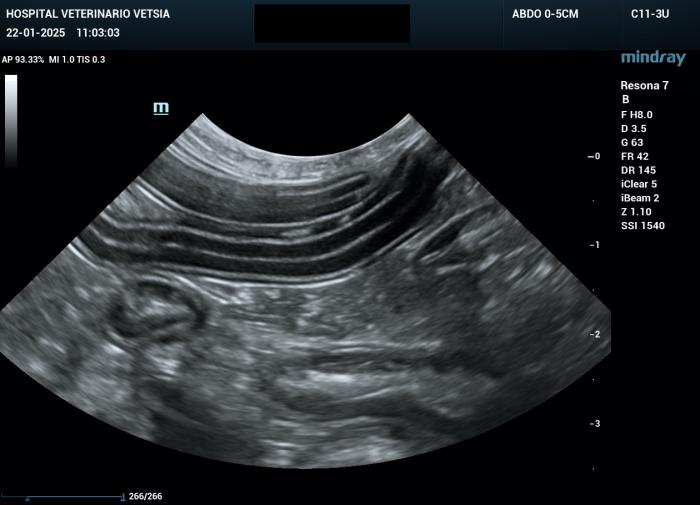

La ecografía abdominal evidenció un engrosamiento moderado de la mucosa y de la submucosa, y leve de la capa muscular del yeyuno y del íleon, generando un efecto masa transmural (Figura 2A-B).

Figura 2A-B. Imágenes ecográficas en las que se aprecia un engrosamiento de la mucosa y submucosa yeyunal, con alteración asimétrica de la capa muscular.

La grasa mesentérica adyacente se mostró moderadamente hiperecogénica, y se identificó una escasa cantidad de líquido libre, insuficiente para toma de muestra.